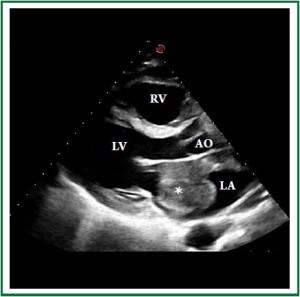

A 46-year-old Caucasian male was admitted to the emergency room with progressive dyspnea, lower limb edema and intermittent fever for 1 month. Past medical history included HIV infection for 20 years, with irregular highly active antiretroviral therapy (HAART) treatment. He had a history of smoking, alcoholism and cocaine addiction. On physical examination, the patient presented with a rapid respiratory rate, blood pressure of 118×68 mmHg and heart rate of 104 bpm. Laboratory data revealed hemoglobin concentration of 6.7 g/dl, white blood cell count of 3.600 /mm3 and platelet count of 22.000 /mm3, with a CD4 count of 49 cels /μl. Computed tomography demonstrated a large, infiltrative, solid mass involving the ascending aorta, pulmonary artery, right ventricle and both atria (Figure 1 and Figure 2) with a lymph node conglomerate in the anterior mediastinum. Transthoracic echocardiography revealed biatrial dilation, mild left ventricular hypokinesia and severe right ventricular impairment. A large echodense mass with irregular borders filled almost completely the left atrium (Figure 3), while another mass was observed inside the right atrium (Figure 4), both attached to the interatrial septum. Increased transvalvular mitral and tricuspid gradients were observed by Doppler study. HAART was started along with intratechal methotrexate, followed by intravenous dexamethasone. Mediastinal biopsy revealed a HHV8-positive PBL. Tumoral cells showed positivity for immunohistochemical markers HHV8, MUM-1, CD138 (focal), CD20 (focal) and Ki67 (high index), whereas CD3 and Epstein-Barr virus (EBV) resulted negative. Bone marrow biopsy showed rare neoplastic cells, compatible with interstitial infiltration by HHV8-positive PBL. Chemotherapy with cyclophosphamide was started. A control echocardiogram after 3 days showed no tumor regression, but significant deterioration of systolic ventricular function. The patient developed hemodynamic instability and worsening of respiratory pattern, requiring ventilatory and hemodynamic support. Despite therapy, the patient died the following day.

Figure 3. Two-dimensional echocardiographic parasternal long axis view showing a large solid mass (*) almost obstructing the left atrium.